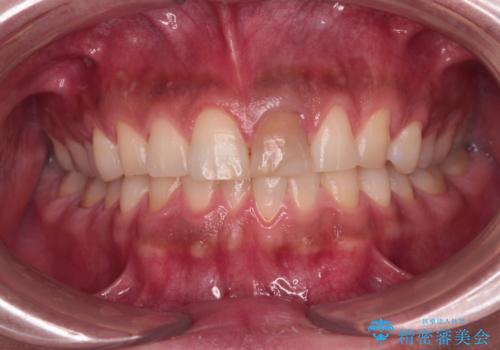

- 神経を取り除いたことで変色した前歯を気にして来院された患者様です。

根管治療はやり直さずに、ファイバーポストを使用した土台を植立してオールセラミッククラウンにて補綴することとしました。

神経を取り除いた歯は時間とともに変色してきます。

クリーニングやホワイトニングでは改善できないため、オールセラミッククラウンなどによる補綴治療が必要となります。